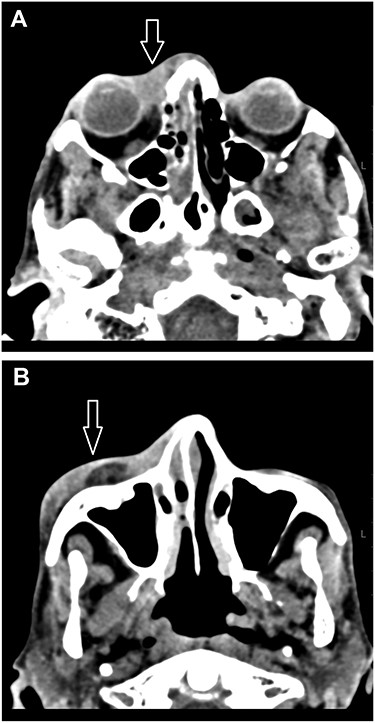

On examination, the patient was found to be afebrile, confused, generally weak and incoherent. Complete ophthalmoplegia despite no marked signs of inflammation with non-reactive pupils and no view of the posterior fundus were marked (Fig. 1). A reduction in right visual acuity from ‘counting fingers’ to ‘light perception’ was noted. An ophthalmic B scan revealed infiltration of the right globe. A computed tomography (CT) scan of the orbit and brain revealed signs of cavernous sinus thrombosis versus orbital cellulitis (Fig. 2A and B).

(A, B) A CT scan of the orbit and brain revealed soft tissue swelling in the pre-septal area (white arrow) and partial opacification of the right nasal cavity (A). The swelling extended to the lateral aspect of the anterior portion of the right zygomatic arch (white arrow; B).